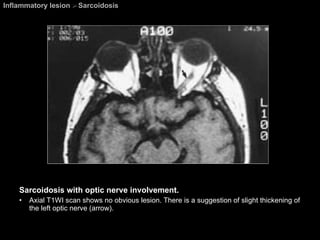

Inflammatory lesion  >  Sarcoidosis Sarcoidosis with optic nerve involvement. Axial T1WI scan shows no obvious lesion. There is a suggestion of slight thickening of the left optic nerve (arrow).